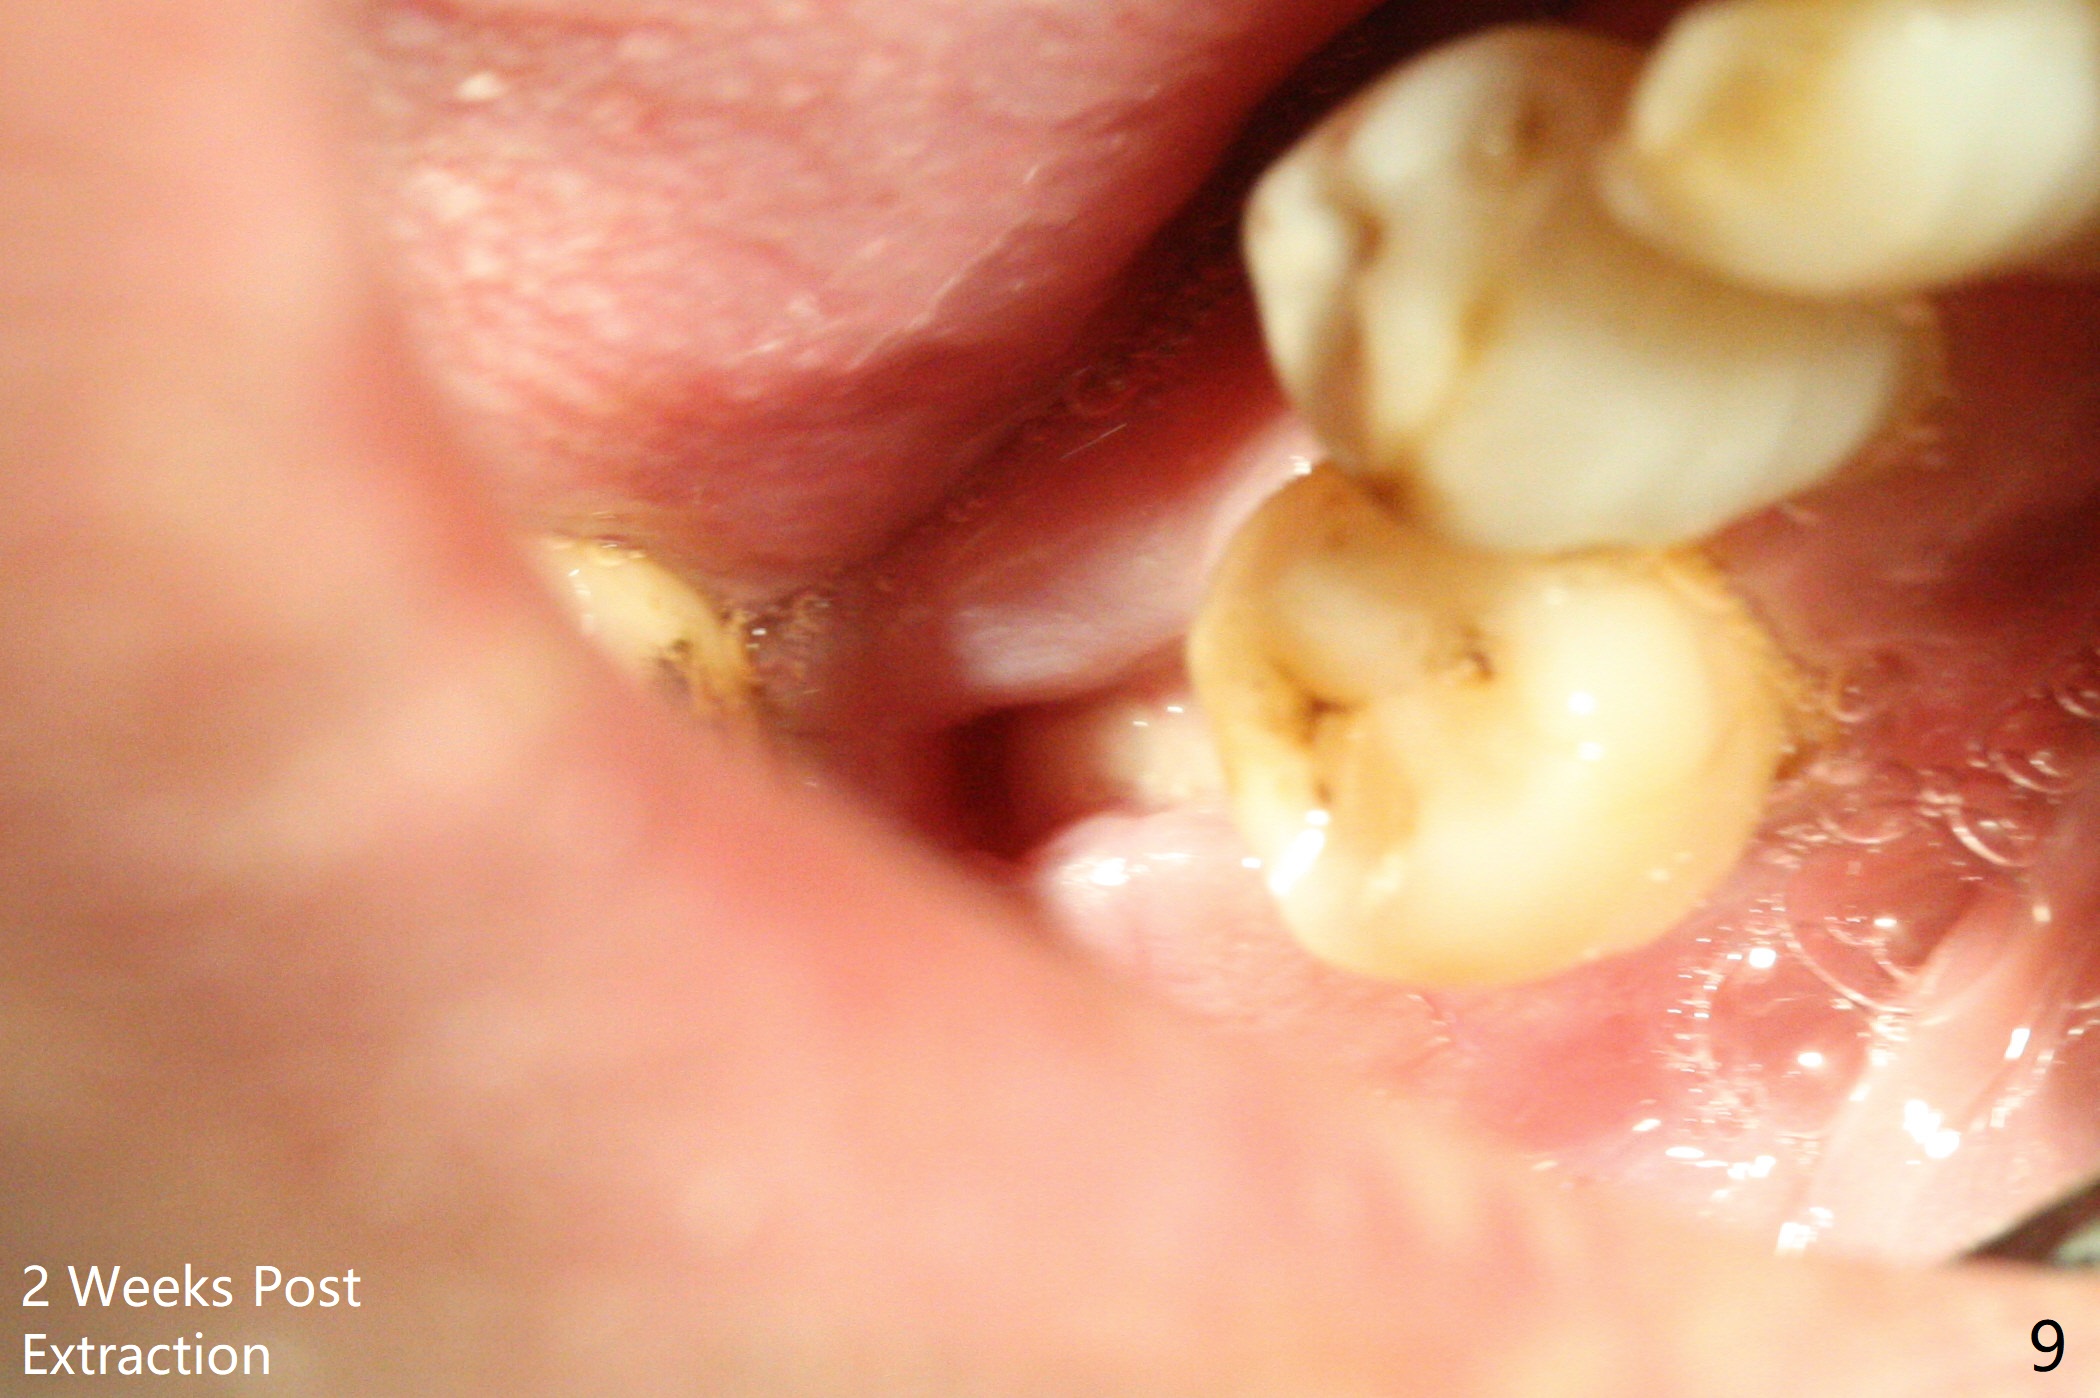

The bone seems to be wide to hold a 5x11.5 mm implant if it is placed early post extraction (Fig.7). Probably due to smoking, the socket appears to heal slow (Fig.8,9). There is mild palpation pain in the buccal vestibule. The tooth #29 remains mobile. The patient is scheduled to return for follow up in 2 months. A 5x5 cm scan is taken for the lower right posterior area for guided surgery.